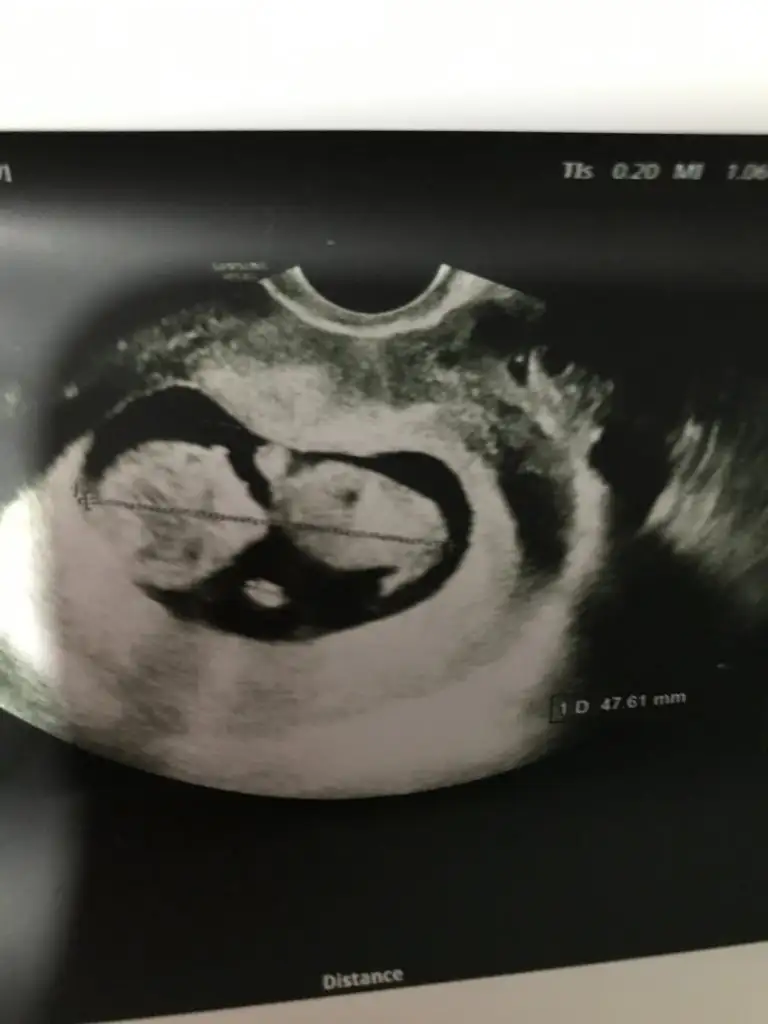

Peki bundan bakabilirmisiniz diğerleri videodan alma olduğu icin net değil Buda alttan muayenedenHiç net değil![]()

Dr tam -----+ nubtan geçmiş ölçümü emin değilim sanki kız 11 12 13 haftalar olursa paylasinPeki bundan bakabilirmisiniz diğerleri videodan alma olduğu icin net değil Buda alttan muayeneden

Erkek gibi sanki başka USG paylasin teyit ederim@ikrameyra yorumlar misin

Başka usg yok doktor kıza benziyor demisti ama net değil demistiErkek gibi sanki başka USG paylasin teyit ederim